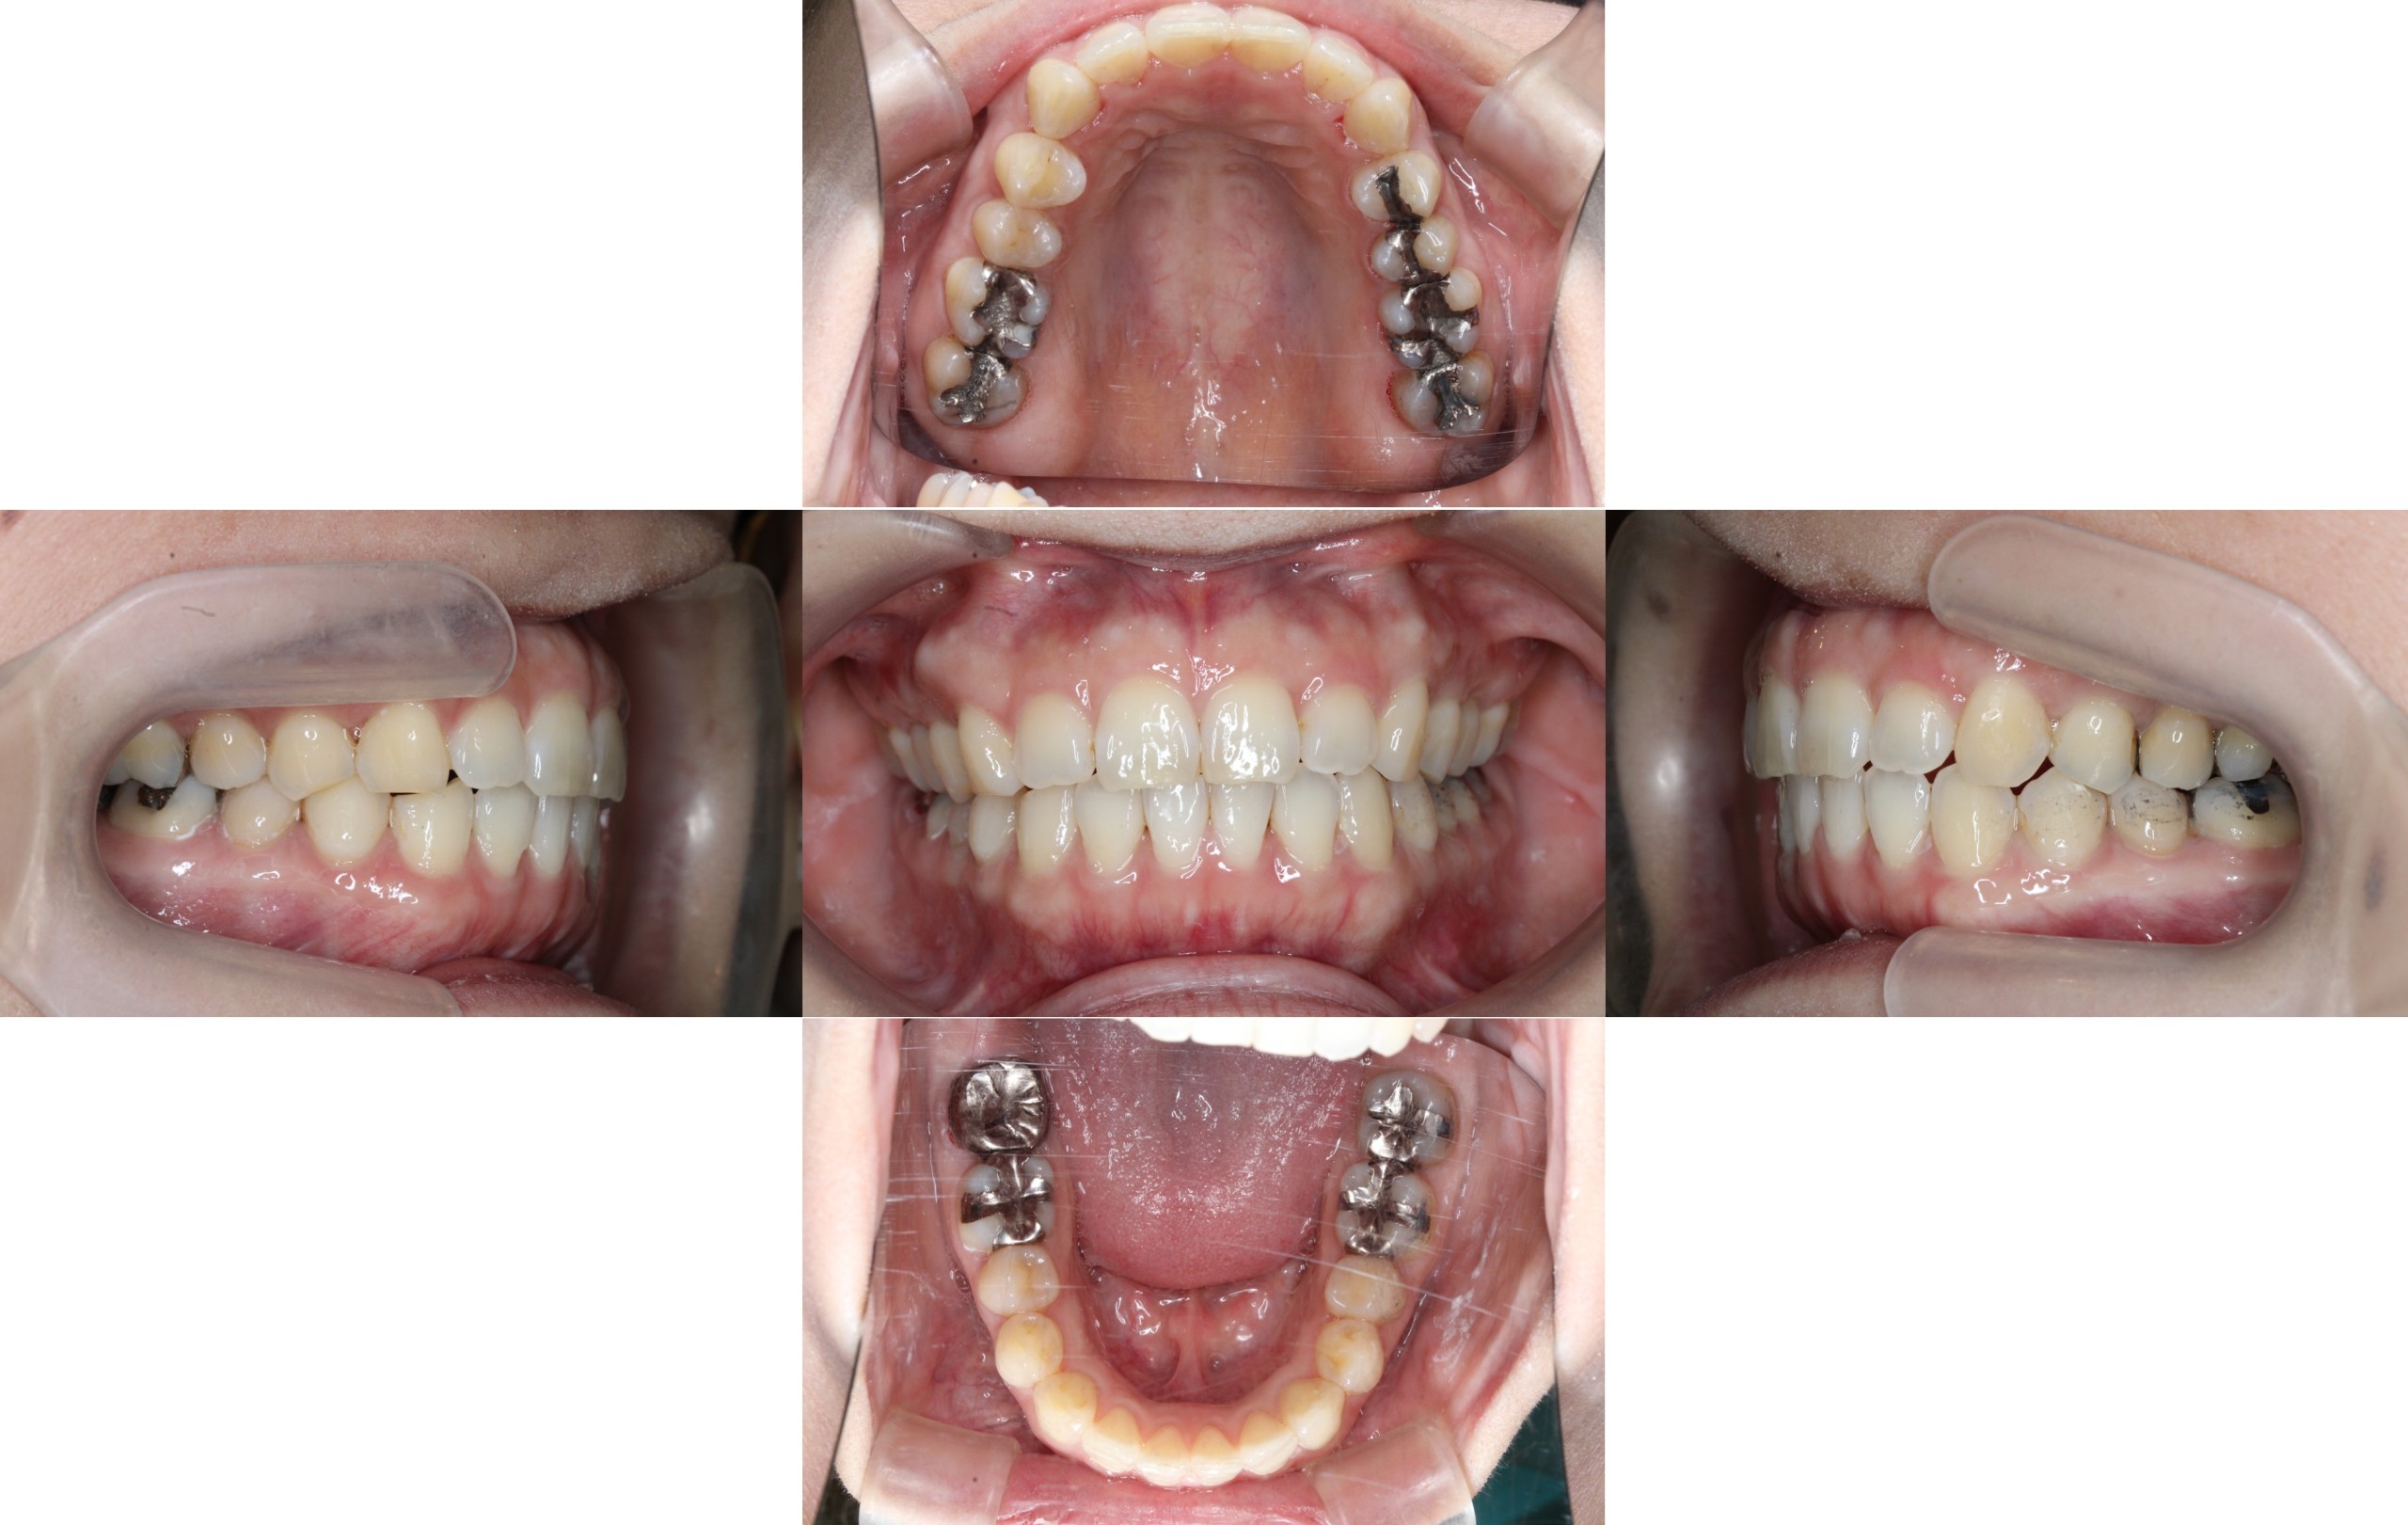

前歯のでこぼこを治したい(治療期間1年2ヶ月/治療回数22回)

Before

After

年齢層

40代

性別

女性

主訴

・└3でっぱり・└2が引っ込んでいる

治療費用

¥1,199,000

治療期間

1年2ヶ月(最終微調整をマウスピース矯正で治療中)

抜歯

非抜歯

矯正の装置

ハーフリンガル矯正

副作用、リスク

歯肉退縮,歯根吸収,疼痛,咬合の違和感,装置の違和感,虫歯,歯肉炎